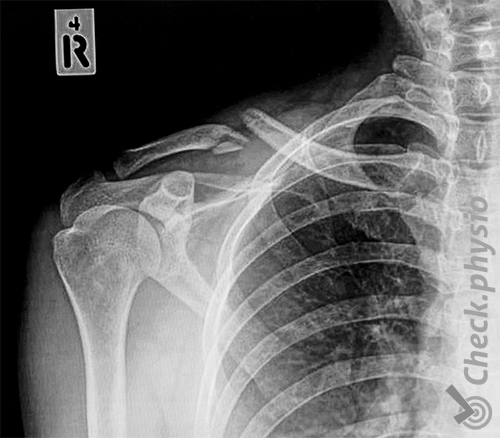

Ein Schlüsselbeinbruch ist nicht schwer zu diagnostizieren, da das Schlüsselbein sehr oberflächlich liegt. Dadurch ist ein Bruch einfach zu sehen und zu fühlen. Ein Röntgenbild wird meist gemacht, um eine Indikation des Bruchs und der Stellung des Schlüsselbeins zu erhalten. Dies gibt Einblick in den Heilungsprozess und kann Probleme mit zugrunde liegendem Gewebe wie Nerven und Blutgefäßen ausschließen.

Wenn sich nach einem Röntgenbild herausstellt, dass der Bruch eine zu große Verschiebung des Schlüsselbeins verursacht oder es sich um einen instabilen Bruch handelt, wird eine Operation in Betracht gezogen.